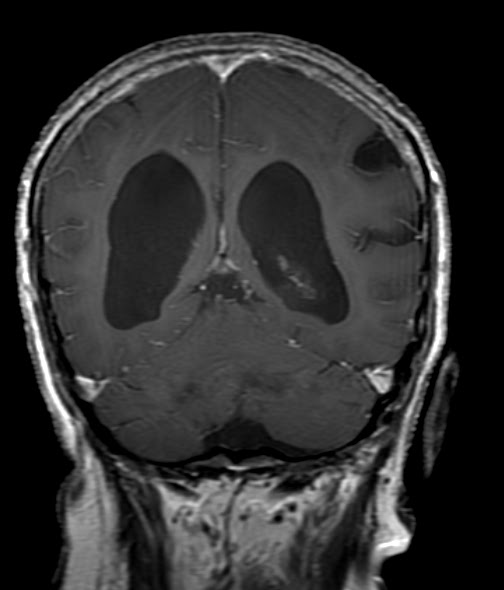

Caso 14

Paciente de 68 años que presenta desequilibrio en la marcha (con

marcha

a pasos cortos y arrastrados), incontinencia urinaria y fallas

en la memoria, de 5 años de evolución. La siguiente RNM de cerebro (cortes

coronales T1 con contraste), muestra claramente una dilatación del sistema

ventricular supratentorial. En el resto de las secuencias no pudo identificase

una clara obstrucción en la circulación del liquido cefalorraquídeo.

Diagnóstico:

Hidrocefalia crónica del adulto.